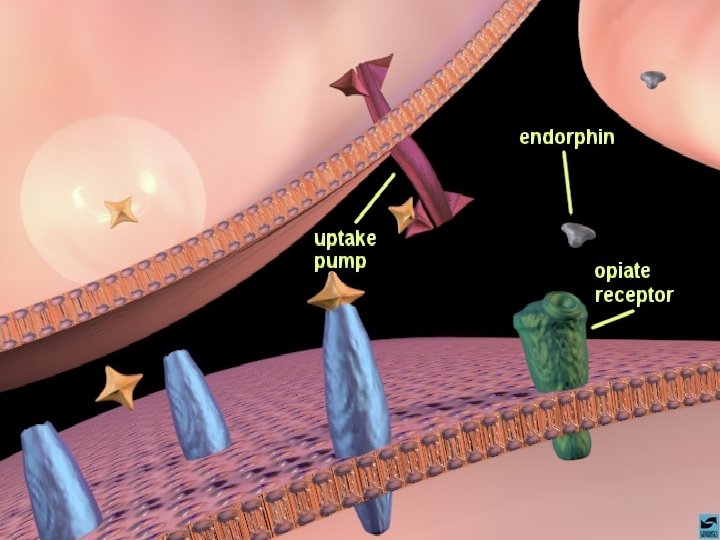

OS OPIÁCIOS EFEITOS CEREBRAIS OS OPIÁCIOS LIGAM-SE AOS RECEPTORES CEREBRAIS DE ENDORFINAS